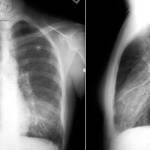

Рентгенограмма грудной клетки выявляет характерные особенности инфекции M. pneumoniae: двустороннее поражение легких, мультифокальное или диффузное затемнение и ретикулярные инфильтраты. В редких случаях плевральные выпоты могут накладываться на паренхиматозные заболевания.

КТ с высоким разрешением может выявить поражение долей и интерстициальные нарушения при пневмонии М. pneumoniae лучше, чем рентгенография грудной клетки. Однако компьютерная томография с высоким разрешением дороже, и облучение увеличивается.

Пациенты с инфекцией M. pneumoniae обычно не кажутся больными, и болезнь часто называют «ходячей пневмонией». Глотка может быть красной, но лимфоузлы не увеличены. Прослушивание грудной клетки и легких выявляет небольшие отклонения. Отличительная черта микоплазменной пневмонии — это несоответствие между физическими данными (относительно немного) и рентгенографическими данными о пневмонии. Может возникнуть одышка, особенно у детей с астмой. Редко может возникнуть молниеносная пневмония с дыхательной недостаточностью.